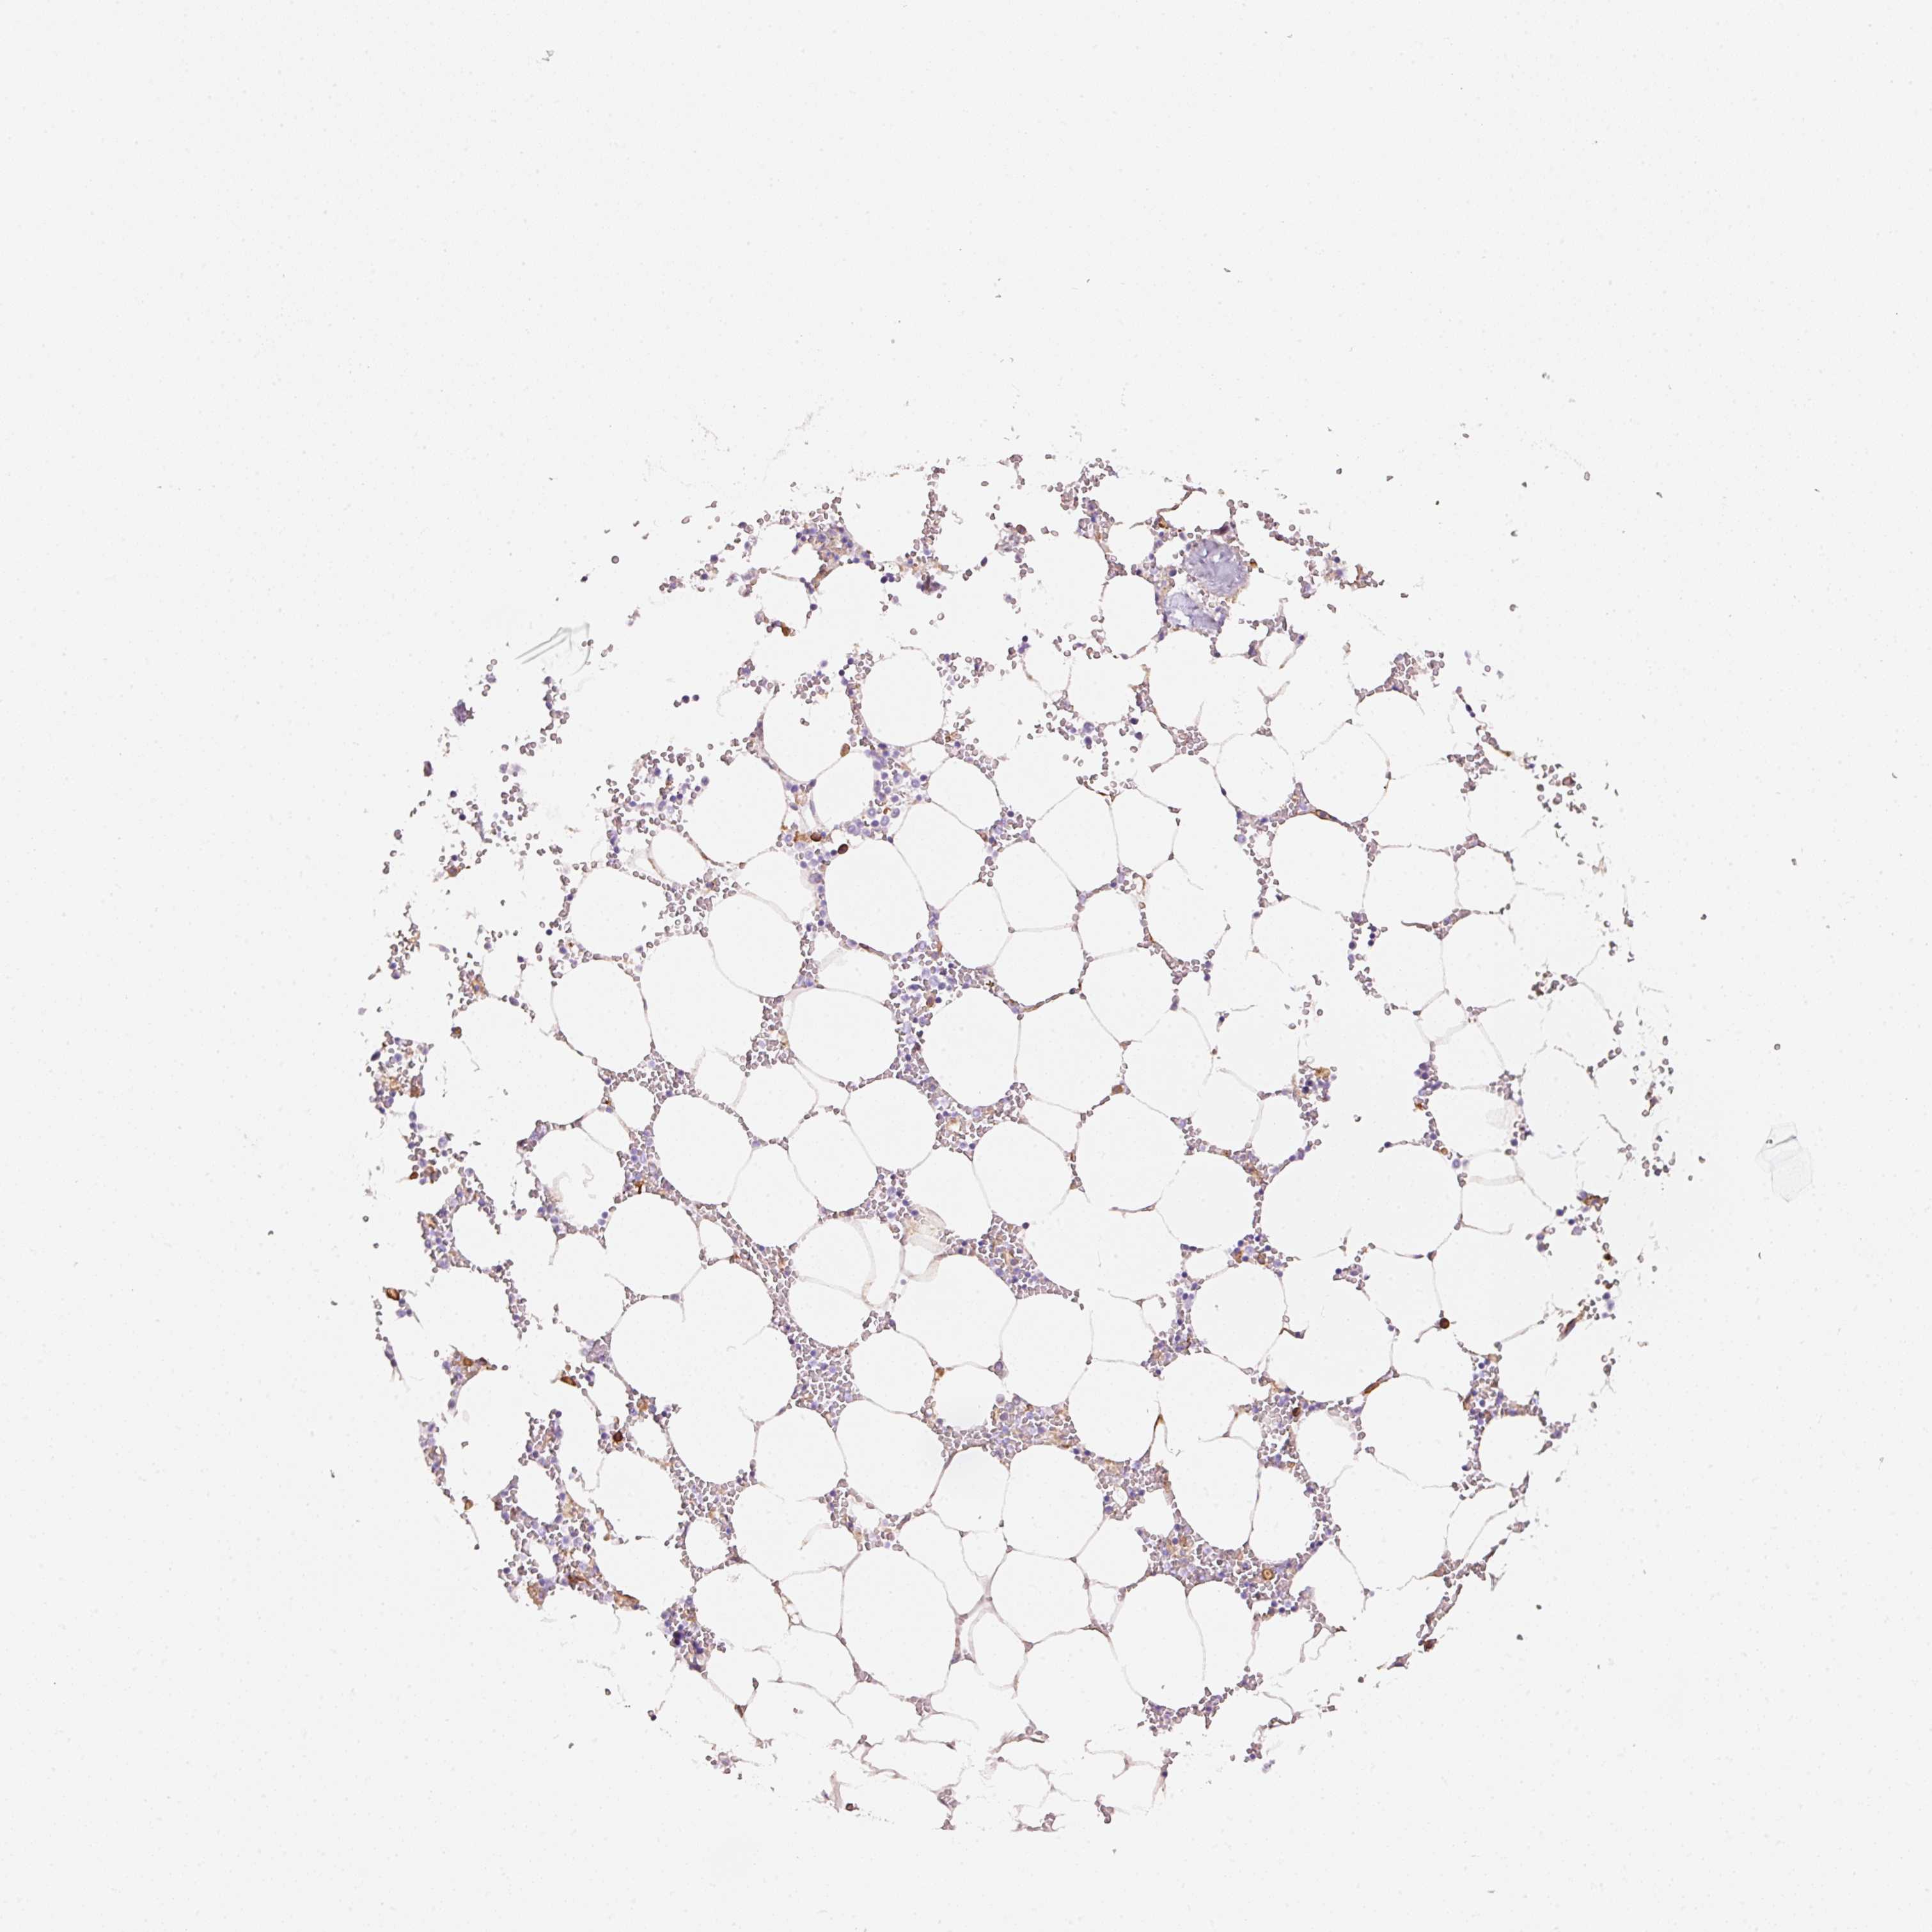

BONE MARROW - Antibody stainingi

Antibody staining in the annotated cell types in the current human tissue is reported as not detected, low, medium, or high, based on conventional immunohistochemistry profiling in selected tissues. This score is based on the combination of the staining intensity and fraction of stained cells.

Each image is clickable and will lead to virtual microscopy that enables deeper exploration of all samples and also displays staining intensity scores, fraction scores and subcellular localization as well as patient and tissue information for each sample.

Antibody HPA036760Antibody HPA036761Antibody CAB000040

Hematopoietic cells MediumNot detectedNot detected